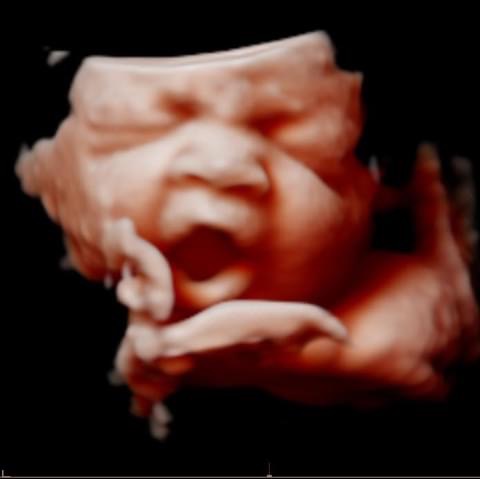

All photos are from our equipment and are of our actual clients.